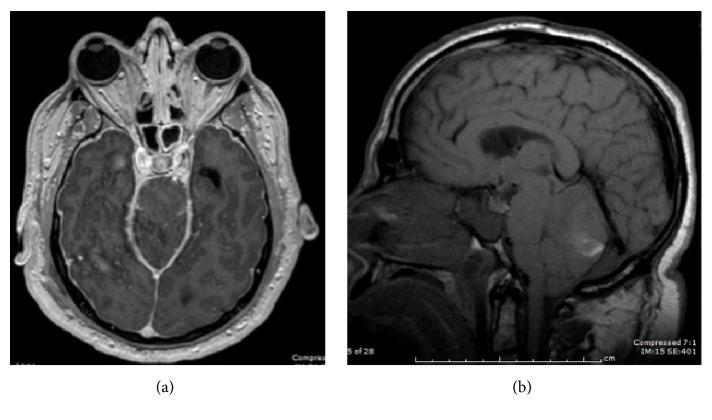

We report the case of a 51-year-old man with no significant past medical history, who underwent elective revision spinal surgery and subsequently developed intracranial hypotension, remote cerebellar haemorrhage (RCH), and mild hydrocephalus on the fourth postoperative day. Remote cerebellar haemorrhage is a known complication of supratentorial surgery. This iatrogenic phenomenon may also occur following spinal surgery, due to dural tearing and rapid cerebral spinal fluid (CSF) leakage, resulting in intracranial hypotension and cerebellar haemorrhage. This complication may result in severe permanent neurologic sequelae; hence, it is of pertinence to diagnose and manage it rapidly in order to optimise patient outcome.

我们报告了一例51岁男性病例,该患者既往无重大病史,接受了择期脊柱翻修手术,术后第四天出现颅内低压、远隔性小脑出血(RCH)和轻度脑积水。远隔性小脑出血是幕上手术的一种已知并发症。这种医源性现象也可能在脊柱手术后发生,原因是硬脑膜撕裂和脑脊液(CSF)快速漏出,导致颅内低压和小脑出血。这种并发症可能导致严重的永久性神经后遗症;因此,快速诊断和处理该并发症对于优化患者预后至关重要。